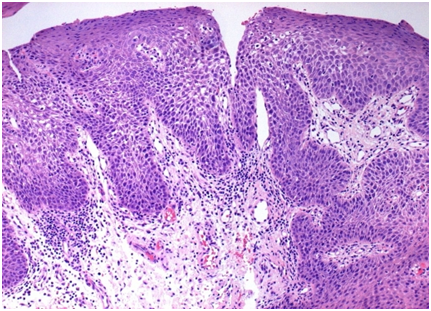

It is discerned by elongated, hypertrophic filiform papillae on the dorsal tongue with hair like manifestations due to inadequate desquamation or increased keratinization of the papillae. The papillae usually 1 mm in length, elongate to 12mm. Women and children are predominantly affected. Heavy smoking, poor oral hygiene, oxidizing mouth washes, candida albicans, certain medications are corroborating factors. Though perceived as Black hairy tongue, the condition demonstrates a black, brown or yellow discoloration, subject to the ingested foods, tobacco, tea and coffee. Metallic taste or gagging is associated Debris entrenched between elongated papillae accounts for the halitosis. Oral hairy leukoplakia must be distinguished from black hairy tongue. Bilateral, vertical white striations usually occur on the lateral tongue (Figure 2).

Figure 2 Psoriform Epidermal Hypertrophy.

3. Image 2 courtesy pathology outlines.